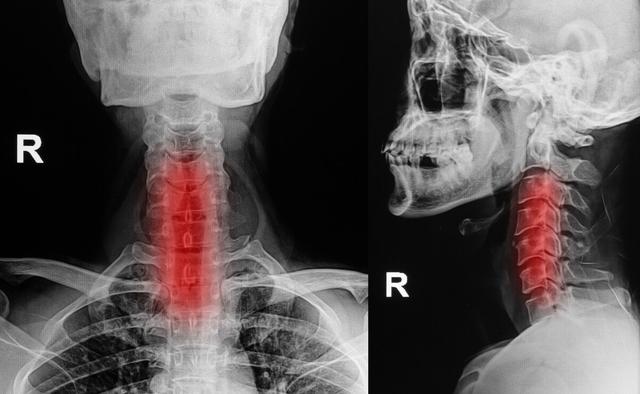

4. spondylose cervicale

L'hypertrophie et l'hyperplasie des vertèbres cervicales, la dégénérescence et la hernie du disque cervical peuvent comprimer la racine du nerf cervical ou la moelle cervicale, déclenchant un engourdissement et une douleur dans les doigts de façon unilatérale ou bilatérale, qui s'étendent progressivement au bras et à l'avant-bras, et entraînent même une altération de la mobilité des membres supérieurs.

如les personnes d'âge moyen et les personnes âgéesEngourdissement de l'extrémité des doigts, en particulierAggravé la nuit pendant le sommeilLa plupart du temps, cette maladie est due à une spondylose cervicale. En raison de la prévalence des personnes d'âge moyen et des personnes âgées, la spondylose cervicale est un problème majeur.ostéophyteDans le cas de la spondylose cervicale, les nerfs cervicaux sont soumis à une stimulation compressive par les os hypertrophiés la nuit pendant le sommeil, ce qui provoque les symptômes correspondants.

L'engourdissement de l'extrémité des doigts dû à la spondylose cervicale se présente le plus souvent comme suitcontinuer à avoir des crises d'épilepsieil est recommandé qu'unRadiographie du rachis cervical, IRM du rachis cervical, etc.Examen pour mieux définir la cause.

1. spondylose cervicale

Pour certains types de patients atteints de spondylose cervicale, l'engourdissement des extrémités des doigts est l'un des symptômes possibles, mais les patients atteints de spondylose cervicale, outre l'engourdissement des doigts, peuvent également être accompagnés d'autres symptômes, tels qu'une faiblesse des membres supérieurs et inférieurs, des douleurs dans la nuque, des difficultés à marcher, des bourdonnements d'oreille, une lourdeur dans la nuque, des vertiges, des nausées et d'autres symptômes. Il n'est pas difficile de diagnostiquer la spondylose cervicale, il suffit de se rendre dans un service d'orthopédie pour effectuer des examens radiologiques et obtenir un diagnostic clair.

La spondylose cervicale, les ostéophytes, les hernies discales, etc., sont susceptibles de bloquer les racines nerveuses qui se ramifient à partir de la moelle épinière, et si elles sont bloquées, un engourdissement des mains peut également se produire, et l'engourdissement des mains se manifeste de la même manière que le syndrome du défilé thoracique. Mais cette affection causée par l'engourdissement des mains s'accompagne d'une gêne, d'une raideur, d'une douleur et de restrictions d'activité plus évidentes au niveau de la colonne vertébrale cervicale.

Lorsque les patients ont des problèmes de colonne vertébrale, la compression des nerfs du plexus brachial entraîne un engourdissement des mains et des douleurs dans les mains, ce qui provoque une insuffisance de l'irrigation sanguine du cerveau, des vertiges et des nausées. L'engourdissement des mains causé par la spondylose cervicale se manifeste principalement par un engourdissement unilatéral, par exemple du pouce et de l'index, ou de l'auriculaire et de l'annulaire, et le patient éprouve une inflexibilité des doigts, comme des difficultés à attacher des boutons et à tenir des baguettes. La manifestation de la spondylose cervicale, outre l'engourdissement des doigts, s'accompagne de douleurs musculaires au niveau du cou et des épaules, de douleurs irradiant dans les membres supérieurs et d'autres symptômes. Par conséquent, lorsque les symptômes d'engourdissement unilatéral des mains apparaissent, il convient de se demander s'il s'agit d'une spondylose cervicale.

5. spondylose cervicale

La spondylose cervicale est le principal facteur conduisant à l'engourdissement des doigts, en raison de facteurs à long terme conduisant à la protrusion des vertèbres cervicales, ce qui comprime les nerfs et les vaisseaux sanguins des deux côtés. La principale cause de l'engourdissement des doigts est la compression du nerf du plexus brachial ou du nerf cervical, de sorte que la lésion du nerf du plexus brachial ou du nerf du plexus cervical ainsi que la lésion des nerfs des membres supérieurs peuvent provoquer un engourdissement des doigts.